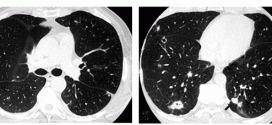

TUMOR DE PULMÓN METASTÁSICO

El tumor de pulmón metastásico. Los pulmones son un par de órganos que dan oxígeno al cuerpo y expulsan el dióxido de carbono, un producto de desecho producido por las células del cuerpo. Los bronquios, por su parte, son unos tubos a través de los cuales llega el aire inspirado desde la boca a los pulmones; se dividen en otros …

CARCINOMA MUCOEPIDERMOIDE PULMONAR

El carcinoma mucoepidermoide pulmonar. Tumor maligno en general y especialmente el formado por células epiteliales. Durante los primeros años de vida de una persona, las células normales se dividen más rápidamente para permitir el crecimiento. El cuerpo está compuesto por billones de células vivas. Las células normales del cuerpo crecen, se dividen formando nuevas células y mueren de manera ordenada. …

CARCINOMA MUCOEPIDERMOIDE DE PULMÓN

El carcinoma mucoepidermoide de pulmón. Tumor maligno en general y especialmente el formado por células epiteliales. Los canceres se dividen en dos grandes categorías de carcinoma y sarcoma. Durante los primeros años de vida de una persona, las células normales se dividen más rápidamente para permitir el crecimiento. El cuerpo está compuesto por billones de células vivas. Las células normales …